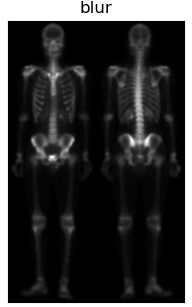

| 对Sobel运算得到的图像进行双边滤波,可以平滑噪声保留边界;在书中利用的为均值滤波,我认为此处由于灰度范围比较窄,实际我也使用了均值滤波进行对比,实际差距不大。但是我觉得运用双边滤波会更好一些。 |

| 最终将各结果进行对比显示 |